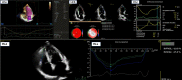

Objectives: Describe the use and findings of cardiopulmonary imaging-chest X-ray (cX-ray), echocardiography (cEcho), chest CT (cCT), lung ultrasound (LUS), and/or cardiac magnetic resonance imaging (cMRI)-in COVID-19 hospitalizations in Latin America (LATAM).

Results: We studied 1,435 hospitalized patients (64% males) with a median age of 58 years classified into three regions: Mexico (Mx), 262; Central America and Caribbean (CAC), 428; and South America (SAm), 745. More frequent comorbidities were overweight/obesity, hypertension, and diabetes. During hospitalization, 58% were admitted to the ICU. The in-hospital mortality was 28%, and it was highest in Mx (37%).The most frequent images performed were cCT (61%), mostly in Mx and SAm, and cX-ray (46%), significant in CAC. The cEcho was carried out in 18%, similarly among regions, and LUS was carried out in 7%, with a higher frequently in Mx. Abnormal findings on the cX-ray were peripheral or basal infiltrates, and in cCT abnormal findings were the ground glass infiltrates, more commonly in Mx. In LUS, interstitial syndrome was the most abnormal finding, predominantly in Mx and CAC.Renal failure was the most prevalent complication (20%), predominant in Mx and SAm. Heart failure developed in 13%, predominant in Mx and CAC. Lung thromboembolism was higher in Mx while myocardial infarction was in CAC.Logistic regression showed associations of abnormal imaging findings and their severity, with comorbidities, complications, and evolution.

Conclusions: The use and findings of cardiopulmonary imaging in LATAM varied between regions and had a great impact on diagnosis and prognosis.